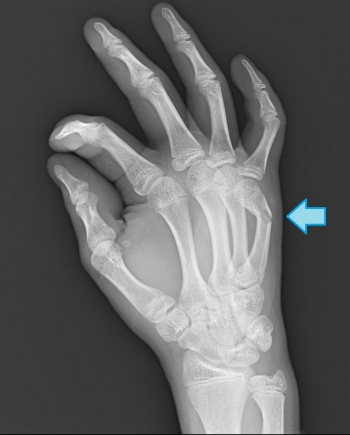

ÃæÀá¹ü¹üÀÞ

´ðÀá¹ü¤ÈÈæ¤Ù¤ë¤ÈÉÑÅÙ¤ÏÄ㤤¡£

·ÛÉô¹üÀÞ¡¢¹ü´´Éô¹üÀÞ¡¢´ðÄìÉô¹üÀÞ¤Ëʬ¤±¤é¤ì¤ë¡£

·ÛÉô¹üÀÞ

¾®»ù¤ËȯÀ¸¤¹¤ë¤Þ¤ì¤Ê¹üÀÞ

ÃæÀá¹ü¤Î·ÛÉô¤ËÑòÃÇÎϤ¬Æ¯¤¤¤ÆÈ¯À¸¤·¡¢ç§¤ÎÄä»ßÉô¤ò»ý¤¿¤Ê¤¤¹üƬ¤¬ÇØÂ¦¤Ë²óž¤¹¤ë¤³¤È¤â¤¢¤ë¡£

¹ü´´Éô¹üÀÞ

¹üÀÞÉô¤¬Àõ»Ø¶þ¶Úç§ÉÕÃåÉô¤è¤ê¶á°ÌÉô¤Î¹üÀޤξì¹ç¡¢ÇØÂ¦ÆÌÊÑ·Á

¹üÀÞÉô¤¬Àõ»Ø¶þ¶Úç§ÉÕÃåÉô¤è¤ê±ó°ÌÉô¤Î¹üÀޤξì¹ç¡¢¾¸Â¦ÆÌÊÑ·Á